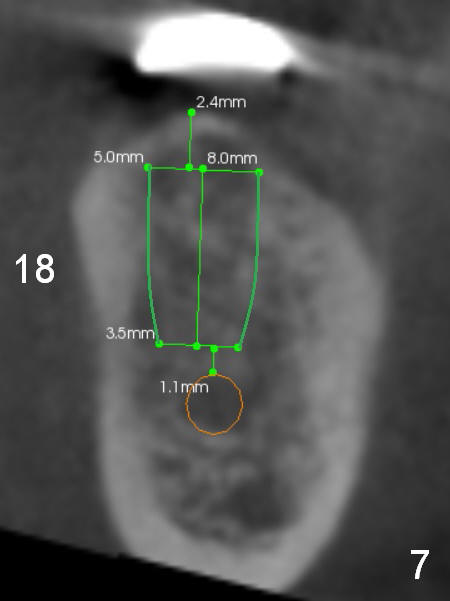

A 69-year-old man would consider implant option for his upper front teeth (Fig.1: #5-9) if there is no separate bone graft procedure. He does not want implants for his lower left molars (#18,19), since he has had a partial denture. In fact the bone at #5-9 is so thin that 2-3 mm 1-piece implants can be placed at #5,7 and 9 (Fig.2-5 (CT coronal sections (B: buccal)) for a 5-unit bridge (Fig.1). To support and increase the longevity of the latter, implants at #18,19 are mandatory (Fig.6,7).

Wheel saws will be used to split the ridge before drilling at #7 (Fig.4). Surgical bur is to be used for ridge reduction prior to osteotomy at #19 (Fig.6), while at #18, osteotomy depth will be 10 mm for 8 mm implant (Fig.7).